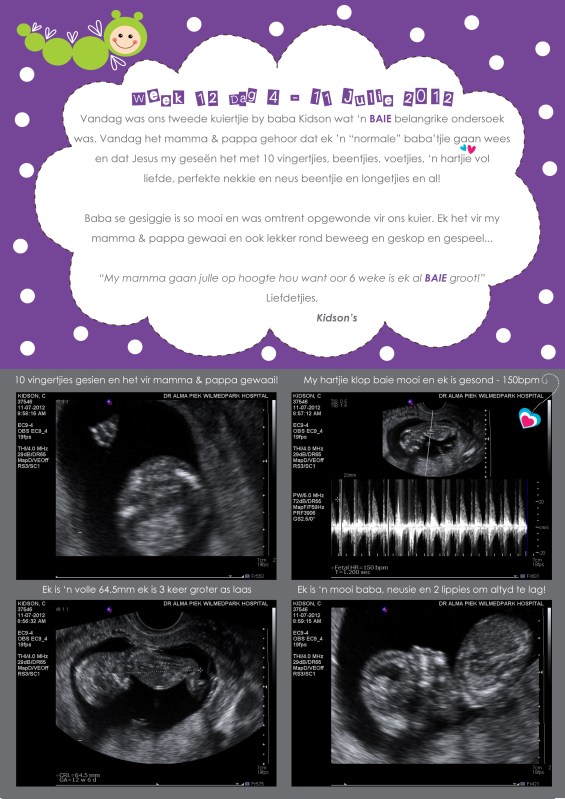

Let me tell you today that it is an absolute miracle to see a little growing person when going for a sonar. Today was a day filled with so many emotions. This was our second visit to the doctor and we had an appointment with a specialist who specializes in analyzing sonar’s and who does the scan for down syndrome etc. Not sure what you call her position but wow what a visit! While being confident that nothing will be wrong there will always be that “stressful” moment to see if everything is ok with baby and that there are no abnormalities.

I’m 12 weeks and 4 days today, expected due date is 19 January 2013 and even though I feel like a mini hippo at the moment it is just so worth it all! I did speak to the doc about my concerns for picking up SO MANY weight and he assured me that I don’t have anything to worry about at this stage and that when he met me I was way to small weighing just under 45kg! He also mentioned that I must remember that the intensity in my training took a huge setback and that I must just relax and stay healthy by making the right nutritious choices. So it is time to make peace and be grateful for every second! So to the ladies feeling a bit fat or bloated we all have those days and there will be better days! Being pregnant is something beautiful and you as a women is precious and beautiful no matter what the scale may show you! Don’t condemn who you are and where you’re at. Look ahead and be confident in who you are!

Baby even waved at us at a stage or that is what mommy believe he/she did ;-). We saw all 1o the fingers, feet, nose, little lips, heard the heartbeat at 150bpm and 64.5mm long. Its really an unbelievable feeling when you hear the heartbeat and see that everything is in place.